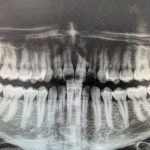

Zunächst führt Dr. Piehslinger ein parodontales Screening durch bei dem die PGU das ist die Parodontale Grunduntersuchung vorgenommen wird. Diese Werte werden in ein Zahnschema eingetragen. Zusammen mit dem Panoramaröntgenbild, welches den Zustand des Zahnhalteapparates zeigt und den gemessenen Werten pro Sextant ergibt sich für das erfahrene Auge des Parodontologen ein klares diagnostisches Bild. Ab Werten von 3 und darüber ist eine Parodontitistherapie notwendig. Dieses Erstgespräch ist kostenfrei.

Panoramaröntgenbild

Mit dem Paro-Status, dem Panoramaröntgenbild und der PGU führt Dr. Piehslinger,  Experte für  Pardontitisbehandlung, ein ausführliches Diagnosegespräch mit Ihnen und erklärt mit dem Zahnschema wo er Handlungsbedarf sieht. Das Panoramaröntgenbild kann sehr schön das Stadium der Erkrankung und den Grad der Beschädigung des parodontalen Gewebes zeigen. Fragen inwieweit der Zahnhalteapparat betroffen ist, wie tief Ihre Zahnfleischtaschen sind und die Prognose für einzelne Zähnen werden in Ruhe erörtert. Dr. Piehslinger klärt Ursachen der Gingivitis und Parodontitis, sowie des Krankheitsverlaufes mit Ihnen ab. Die Besprechung der Ziele und Wünsche betreffend einer möglichen prothetischen Versorgung sowie Informationen zu Risken, Erfolgsaussichten und Bedeutung Ihrer Mitarbeit bei der häuslichen Mundhygiene runden das Diagnosegespräch ab. Die Behandlung der Parodontitis erfolgt dann in 3 Phasen von individueller Länge.  Die notwendigen Behandlungsschritte bespricht Dr. Piehslinger mit seinem Behandlungsteam.